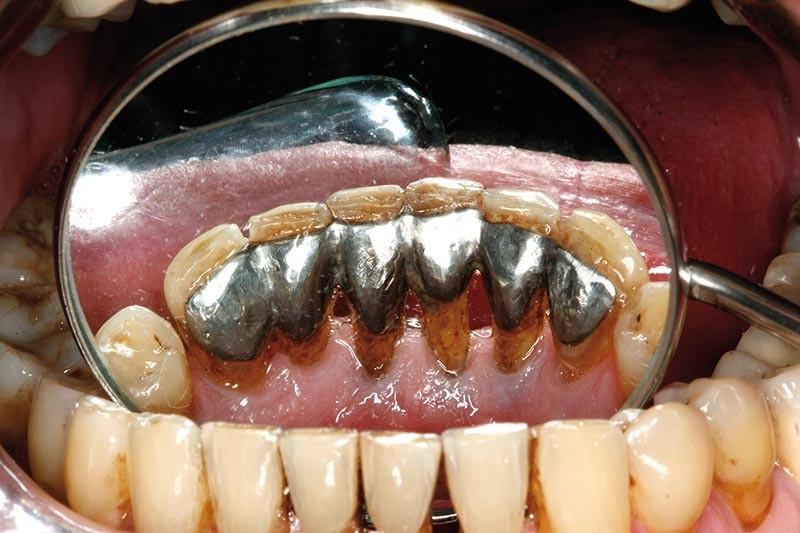

Un montage en articulateur des moulages permet d’observer en relation centrée (RC) de meilleures conditions d’affrontement des dents antérieures. La proposition thérapeutique est la réfection du bridge existant, une équilibration occlusale par coronoplastie des secteurs postérieurs pour stabiliser les appuis occlusaux en RC et la mise en place d’une contention dans le secteur antérieur mandibulaire. Une maquette prothétique permet la réalisation d’un bridge provisoire dans une position corrigée (fig. 4).